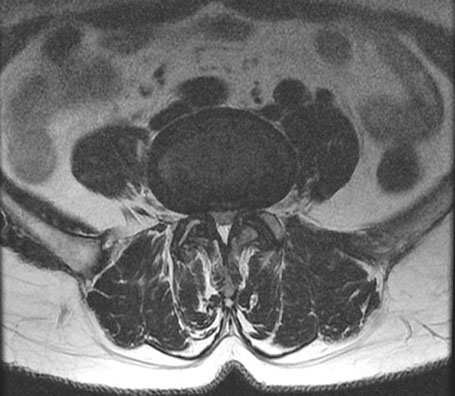

※ After 사진은 6개월 후 촬영된 모습으로, 파열된 디스크가 깨끗하게 흡수된 것을 확인할 수 있습니다.

허리디스크는 비수술 치료를 잘 받으면 튀어나온 수핵이 깨끗하게 흡수되어 없어지는 경향이 있습니다. 특히 파열이 심할수록, 디스크가 찢어져 수핵이 많이 튀어나올수록 오히려 더 잘 흡수되는 경향이 있습니다. 정확히 말하자면, 찢어진 디스크 안으로 재흡수되는 것이 아니라 우리 몸이 튀어나온 디스크를 이물질로 인식해 녹여서 몸속으로 흡수되어 없어지는 것입니다.